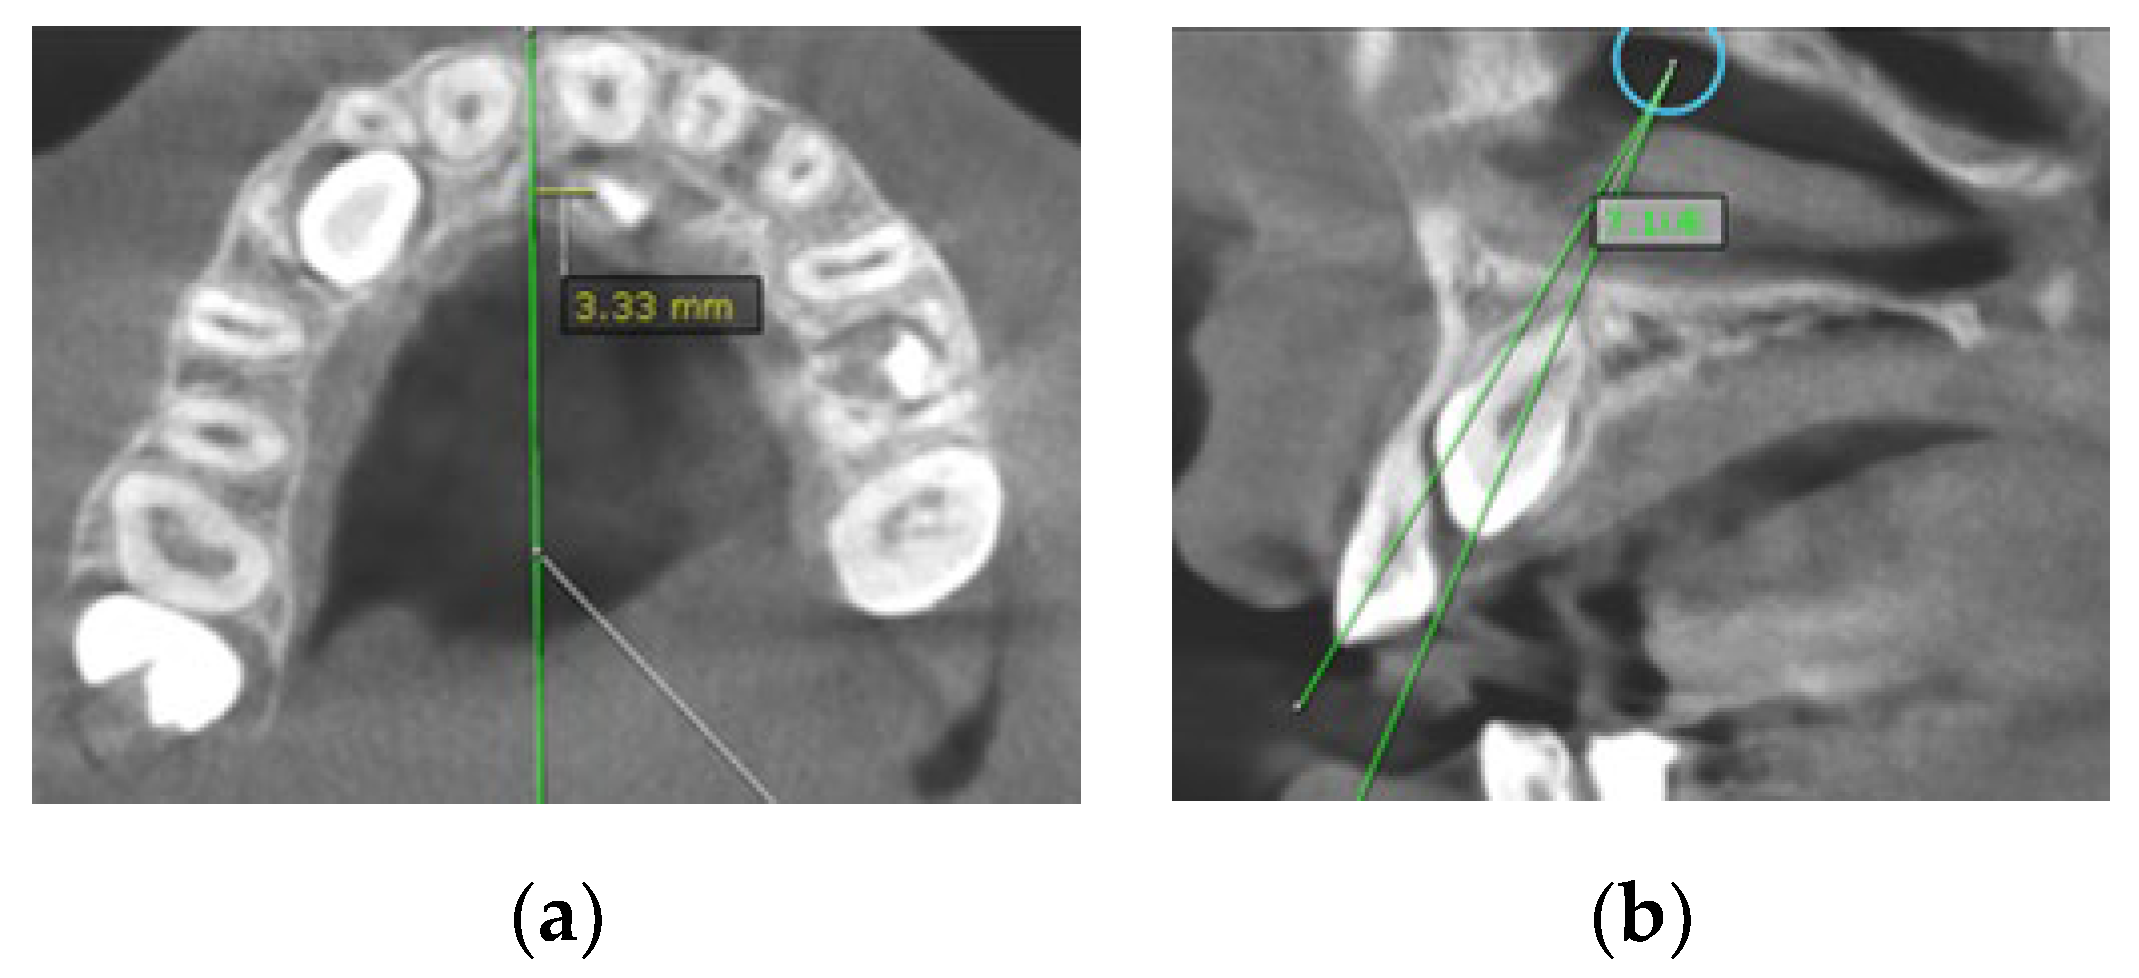

- Sagittal location (labial, palatal or median) using sagittal and coronal CBCT scans (Figure 1a);

- Horizontal position of the canine cusp tip; the canine was observed to overlap with adjacent teeth using sagittal or coronal CBCT scans. It was assigned according to Ericson and Kurol [17] (sector 1: canine overlapping by up to half the width of the lateral incisor; sector 2: canine overlapping by over half the width of the lateral incisor; sector 3: canine completely overlapping with the lateral incisor; sector 4: canine overlapping by up to half the width of the central incisor; sector 5: canine overlapping over the midline of the maxilla) (Figure 1b);

- Distance of the impacted maxillary canine cusp to the midline (measured on axial CBCT scans) (Figure 2a);

Figure 1. (a) Occlusal reference arch–location of impacted maxillary canines in axial plane; (b) horizontal position of canine cusp tip: the canine overlap with adjacent teeth in coronal plane (right maxillary impacted canine in sector 2 ad left maxillary impacted canine in sector 4).Figure 1. (a) Occlusal reference arch–location of impacted maxillary canines in axial plane; (b) horizontal position of canine cusp tip: the canine overlap with adjacent teeth in coronal plane (right maxillary impacted canine in sector 2 ad left maxillary impacted canine in sector 4).

Figure 2. (a) The distance of maxillary canine cusp to midline (measured on CBCT images in axial plane); (b) Angle between long axis of impacted maxillary canine and long axis of adjacent lateral incisor measured on CBCT images in sagittal plane.Figure 2. (a) The distance of maxillary canine cusp to midline (measured on CBCT images in axial plane); (b) Angle between long axis of impacted maxillary canine and long axis of adjacent lateral incisor measured on CBCT images in sagittal plane.